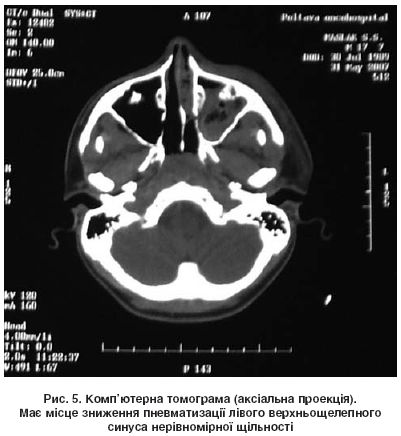

Для оцінювання запальних змін у навколоносових пазухах традиційно використовують рентгенографію в носолобній проекції (рис. 4). Проте звичайна рентгенограма часто не дає змоги одержати точні дані про локалізацію й характер патологічного процесу в синусах і стан внутрішньоносових структур. У разі ускладнень бактеріального синуситу вона не може інформувати про поширення патологічного процесу в порожнину черепа або орбіту, а оцінка стану клітин ґратчастого лабіринту носить орієнтовний характер. Найінформативнішим діагностичним методом є комп’ютерна томографія (КТ), за допомогою якої можна отримати просторове відображення внутрішньоносових структур і навколоносових пазух, а також визначити характер анатомічних порушень, оцінити характер тканин за їх рентгенологічною щільністю (рис. 5). Але найціннішим є те, що комп’ютерні томограми (в аксіальній і коронарній проекціях) є «картою» для планування хірургічного втручання й «путівником» для хірурга під час проведення ендоскопічної ендоназальної операції.